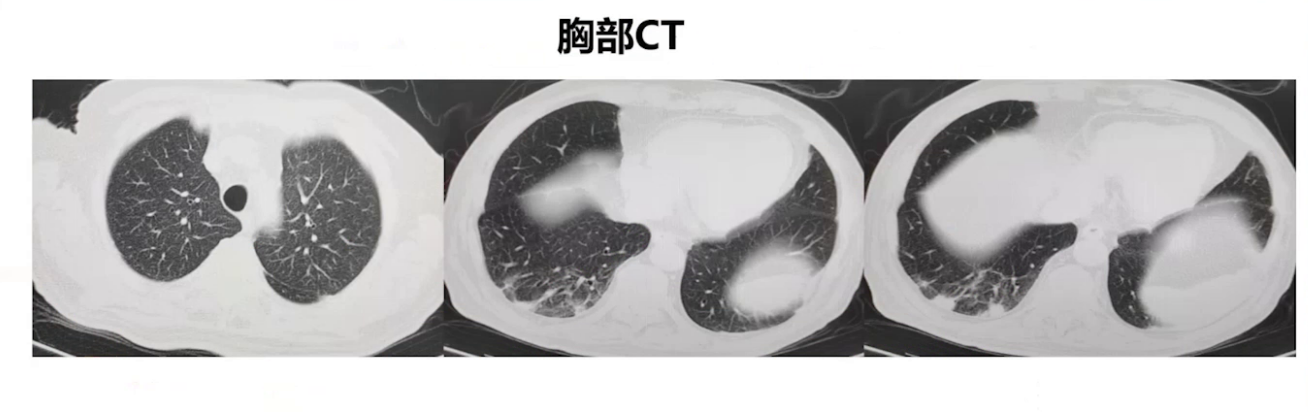

患者两月余前突发胸痛、胸闷、气短,在A医院确诊为急性心肌梗死,接受冠脉支架植入术后转入ICU治疗,后症状缓解出院。出院当日开始低热,体温最高37.7℃,之后胸闷气短加重,于B院诊断为新冠感染,血培养提示耐碳青霉烯的肺炎克雷伯菌,经对症治疗后出院。一周前患者再次发热,体温最高达39.2℃,伴有寒战、咳嗽咳痰,自行服药效果不佳,遂来我院。血常规示白细胞正常,中性粒细胞百分比75.1%,PCT 1.52ng/mL,CRP 56mg/L,胸部CT显示双肺水肿伴右肺下叶感染性病变及双侧胸腔积液,腹部CT提示前列腺增生伴囊性灶,诊断为脓毒症。当地医院予比阿培南联合阿奇霉素抗感染等治疗,症状无明显改善,转院前复查炎症指标升高,患者遂至我院急诊,以脓毒症收入院。

治疗过程中,患者体温在更换药物前已有好转,更换药物后体温平稳,肺部CT显示右肺下叶感染性病灶明显好转,炎症指标也呈好转趋势,但PCT未进行性下降,略有升高,这引发了对是否存在其他感染灶的疑虑。